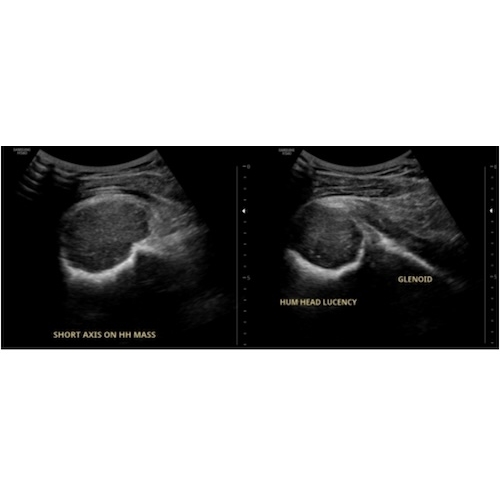

| Lurking In The Acoustic Shadows: Uncovering An Uncommon Diagnosis With Ultrasound - Page #3 | |||